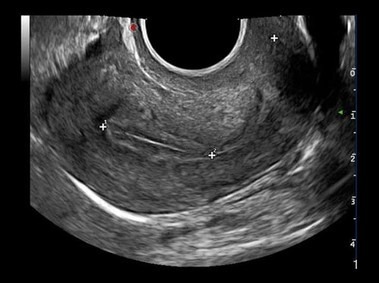

Pelvic or Gynecological Ultrasound

Uterus

A pelvic ultrasound will be requested if you experience lower abdominal pain or abnormal menstrual bleeding.  A pelvic ultrasound can also be performed as a routine examination.

The following organs can be evaluated with a pelvic scan:

Bladder, uterus, ovaries and surrounding soft tissue.

A pelvic ultrasound can be performed transabdominal (from the top of your stomach) or transvaginal (an internal ultrasound)